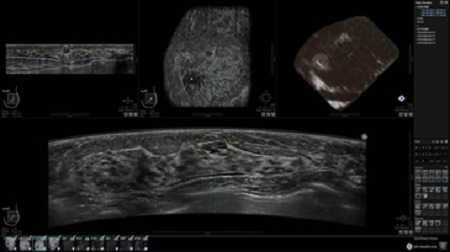

• Получение объемных 3D изображений с возможностью покадрового просмотра

• Настраиваемые рабочие протоколы

• Алгоритмы обработки изображений: алгоритм однородности изображения ткани (TEA), подавление зернистости, компенсация акустической тени от соска (NSC), определение границ молочной железы (BBD), определение стенки грудной клетки

• Получение изображений в поперечной плоскости (в реальном времени) и в коронарной плоскости (статическая, для указания нахождения соска)

• Встроенный сверхширокий вогнутый датчик C15-6XW: диапазон частот: 4 - 15 МГц; длина апертуры: 15,3 см; длина сканируемого участка: 16,9 см; количество элементов: 768

• Глубина сканирования до 5 см.

• Получение одного объемного изображения менее чем за 60 секунд